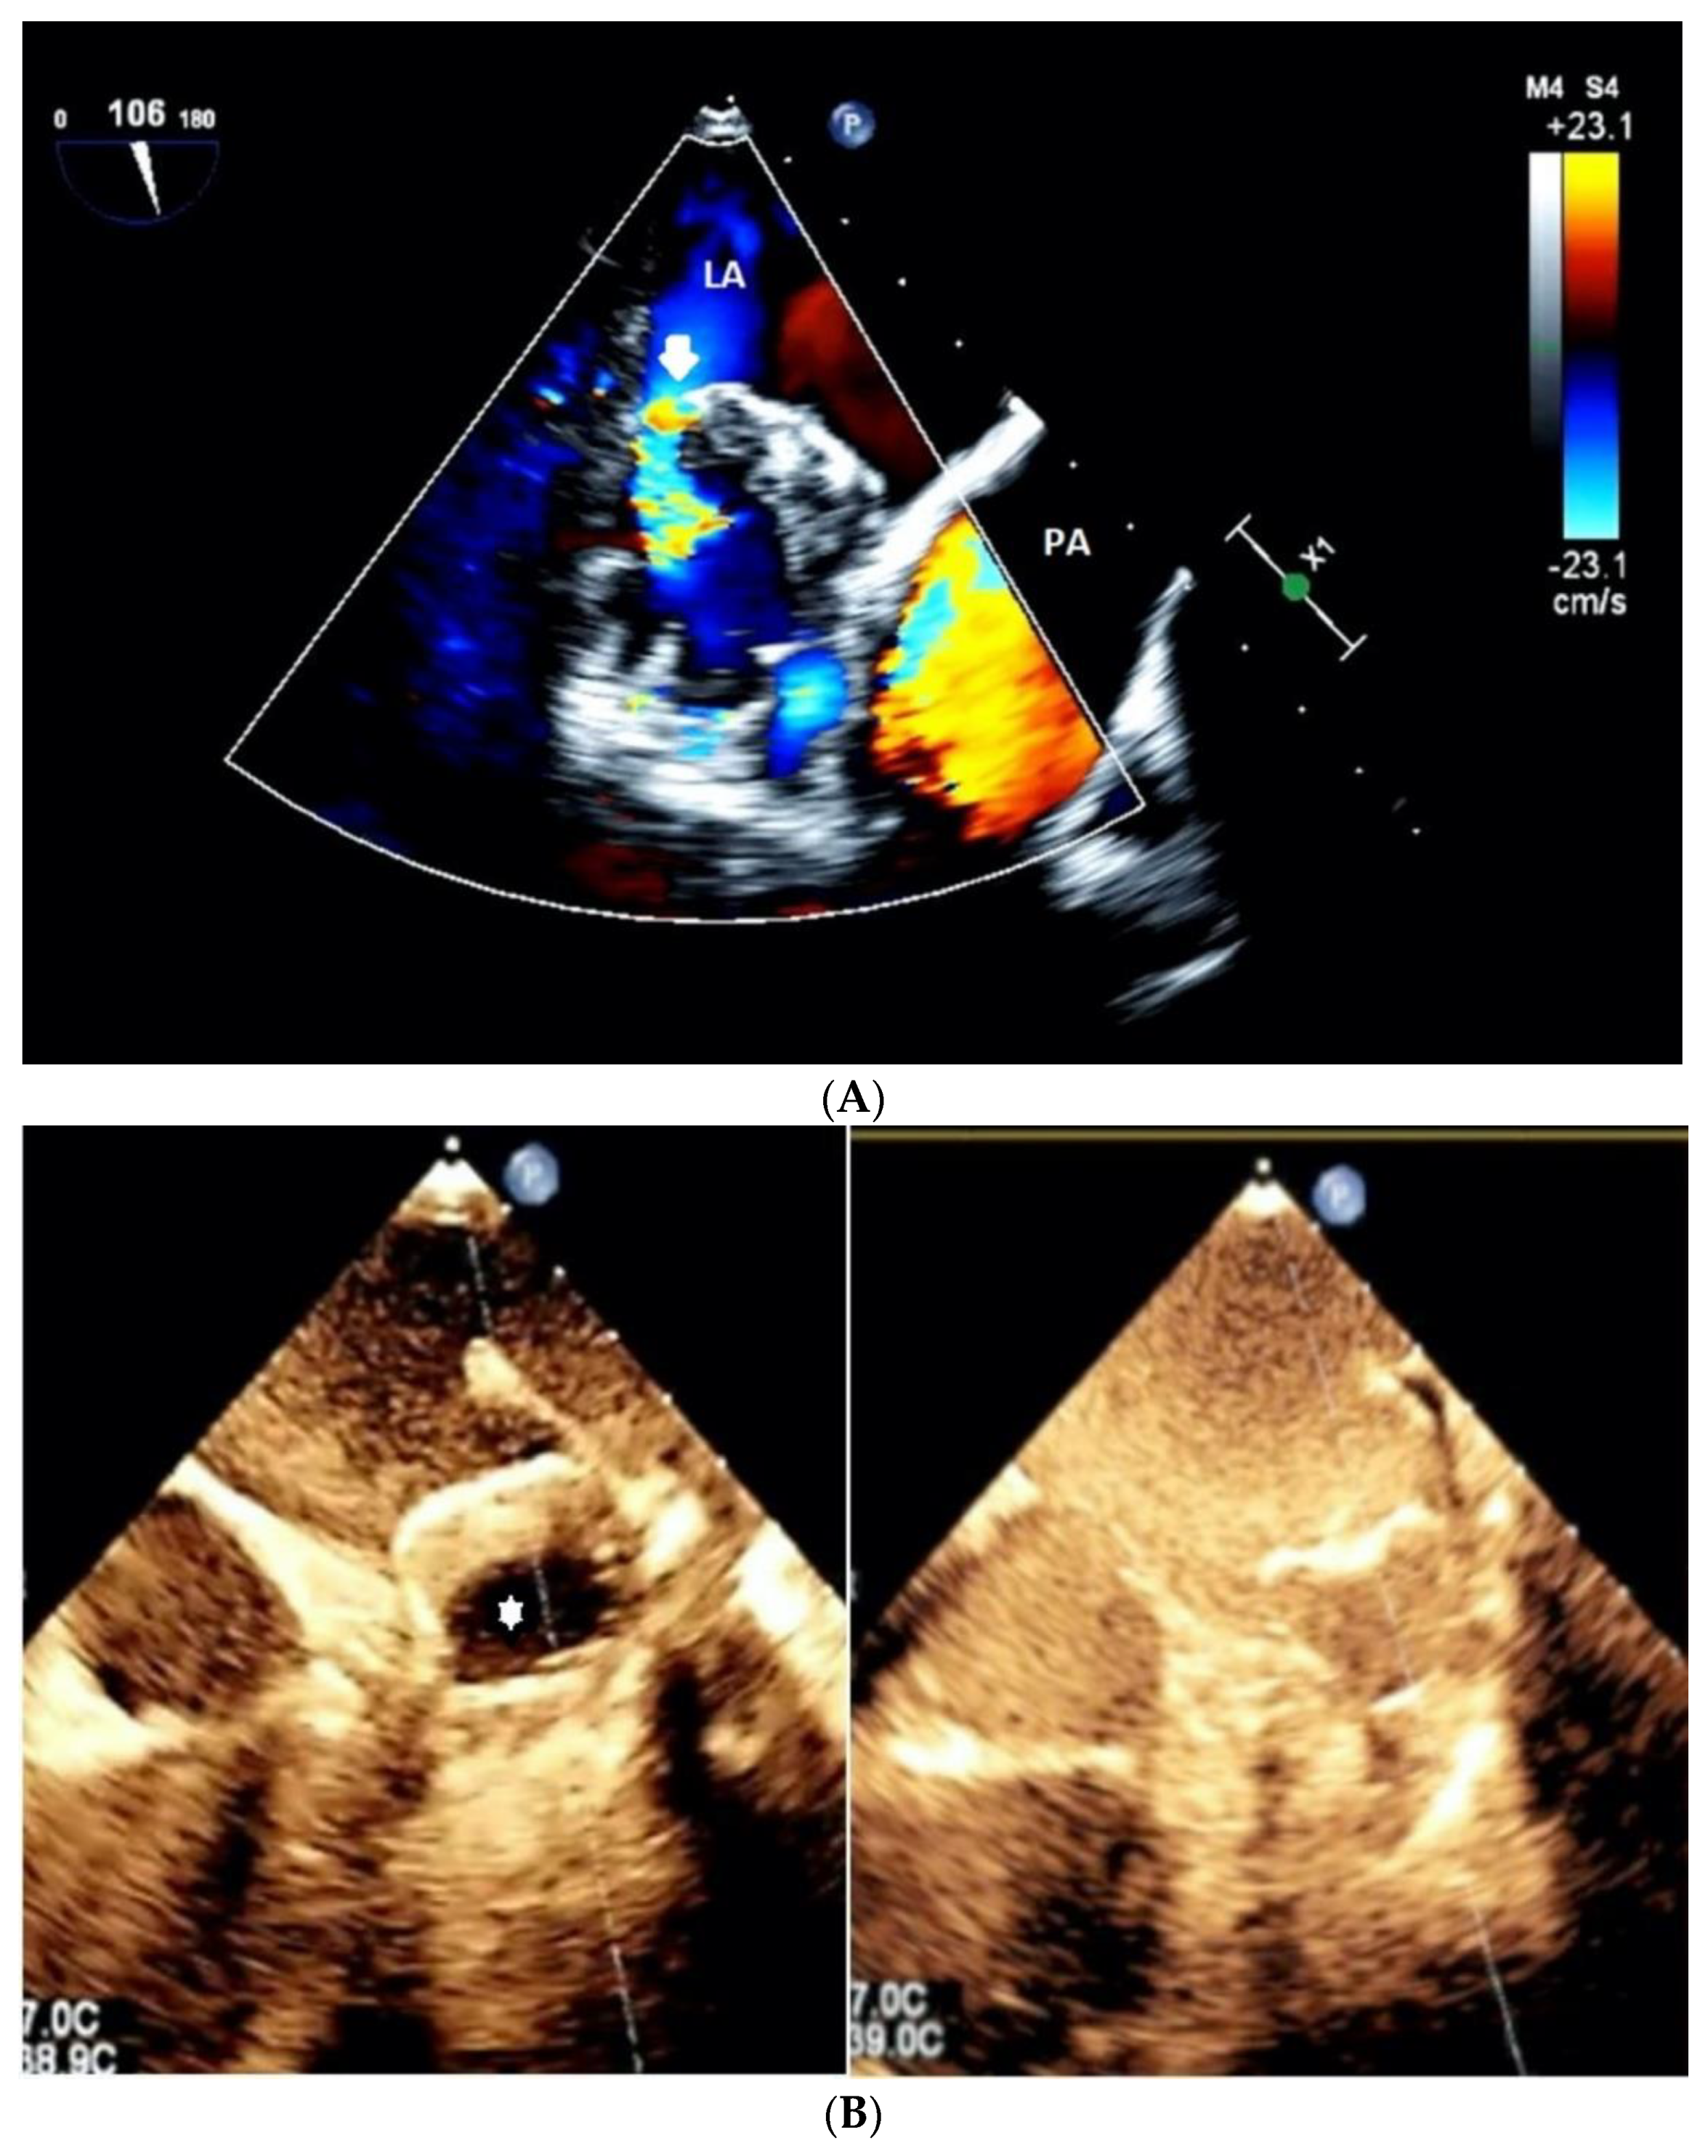

2.2. Transesophageal Echocardiography